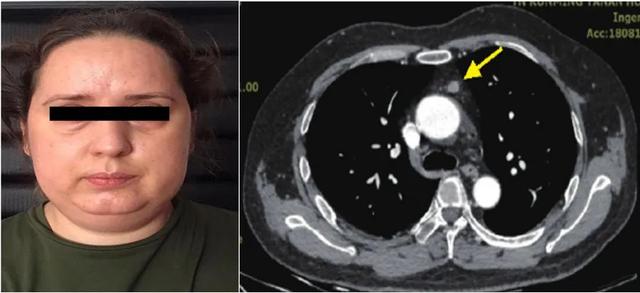

病例介绍 -1患者,女,59岁,体重增加半年,反复头昏3个月余。患者半年来无明显诱因体重增加10 kg,3个月前出现头昏,伴双下肢乏力。在当地医院测血压最高达200/140 mmHg,服用"厄贝沙坦氢氯噻嗪、盐酸特拉唑嗪、硝苯地平控释片、美托洛尔片"控制血压,血压波动在"140 ~ 180 / 100 ~ 120 mmHg",心率120 ~ 160次/min。无特殊遗传病史,无"高血压"家族史。入院体检:脉搏130次/min,血压180 / 125 mmHg。满月脸,水牛背,向心性肥胖,全身多毛,面部及背部多见痤疮,全身皮肤色素沉着,面部色素沉着较明显。双侧腋窝外侧及腹部可见多条横径超过1 cm的紫纹。病例问题-1库欣综合征定性诊断的筛查试验有哪些?

手术病理诊断:伴有ACTH异位分泌的纵隔副神经节瘤。病例图片

外周血ACTH明显升高。大小剂量地塞米松抑制试验,皮质醇均不能被抑制。且大剂量地塞米松抑制试验中皮质醇和ACTH出现逆向升高。结果提示:ACTH依赖性库欣综合征。病例问题-2库欣病和异位ACTH综合征的鉴别有哪些? 手术病理诊断:伴有ACTH异位分泌的纵隔副神经节瘤。病例图片

手术病理诊断:伴有ACTH异位分泌的纵隔副神经节瘤。病例图片 既往笔记促肾上腺皮质激素依赖性库欣综合征的药物治疗(米非司酮)662025-02-10